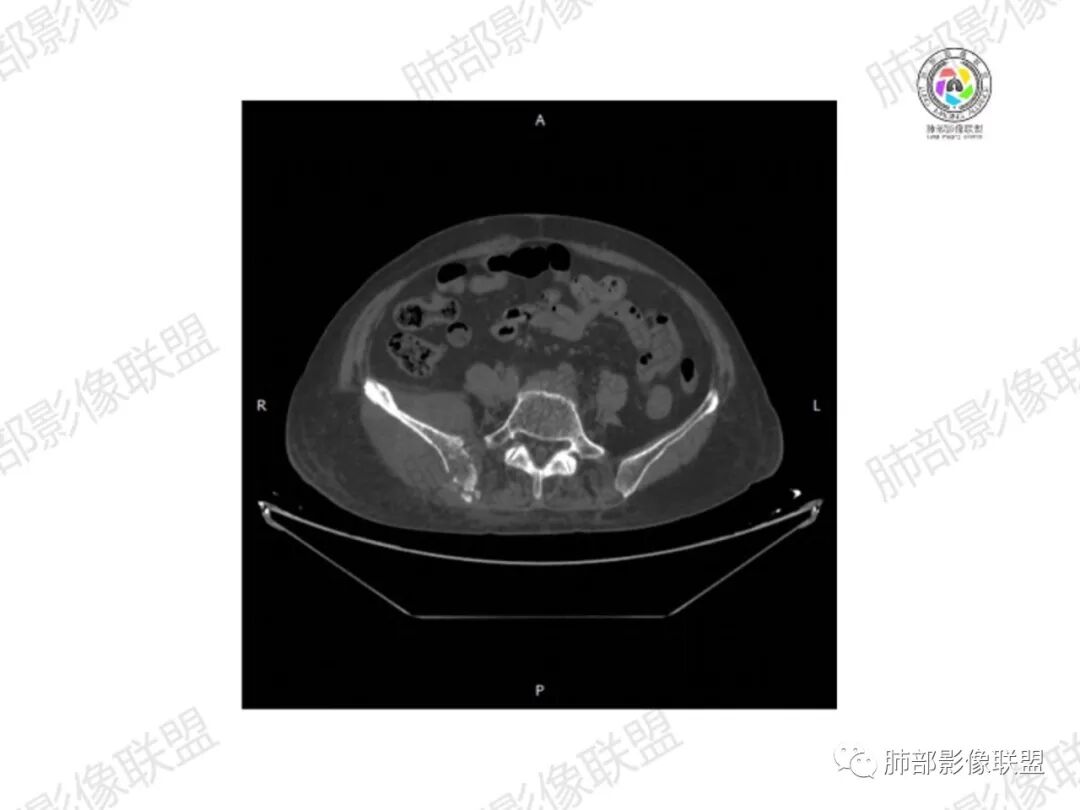

2.右髂骨轻度变形伴广泛骨质吸收破坏,边界不清且突破骨皮质。近中线区以溶骨性破坏为主,髂骨翼一侧则成骨性改变明显,骨表面见垂直骨针或花边样高密度瘤骨。

3.患骨多处皮质断裂,符合病理性骨折。注意折端可能会形成骨痂,但本例无论是形态还是部位都不符合骨痂。

4.患骨两旁(即盆骨内外)见边界不清的较大范围软组织快影,其间偶见骨化影。

1.边界不清的骨质吸收破坏,溶骨明显,骨皮质突破,软组织肿块,种种迹象表明其恶性无疑!

2.但注意这是有“成骨”的恶性骨肿瘤!我们知道老年患者的骨原发性恶性肿瘤“成骨”非常少见。少数转移瘤可为成骨型或混合型,女性患者如乳腺癌骨转移等。在男性,最典型的成骨转移是前列腺癌。

本例右侧髂骨具有较为典型的“骨肉瘤”影像学特征,有边界不清的吸收破坏、有新生骨、形成软组织肿块等等。